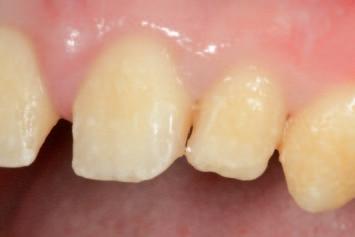

n The tooth reduction guide is tried into the mouth to confirm complete seating and to assess the extent of the anticipated interferences clinically (Figure 2).

FIGURE 2: Initial seating of the preparation guide on the dentition allows the clinician to visualise the intended outcome of this treatment step.

A C B

The external contours of the guide correspond to the planned final contours of the definitive restoration. Regions of the underlying dentition that protrude from the guide windows represent interferences, which must be selectively reduced to achieve the intended outcome. Importantly, this will act as a preliminary reduction, as an initial step prior to conventional tooth preparations for crowns.